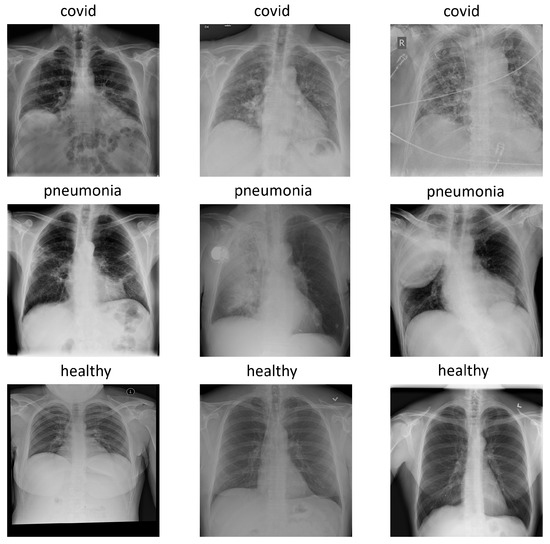

The version used for the experiments was COVIDx7A, which contains 16,690 images with three classes: pneumonia, healthy, and covid. Each image has a 1024 × 1024 size and, for simplicity, is represented in the RGB format with replicated channels. Figure 1 shows an example of each class in the COVIDx dataset.

Figure 1.

Examples of each class in COVIDx dataset: covid, pneumonia and healthy.